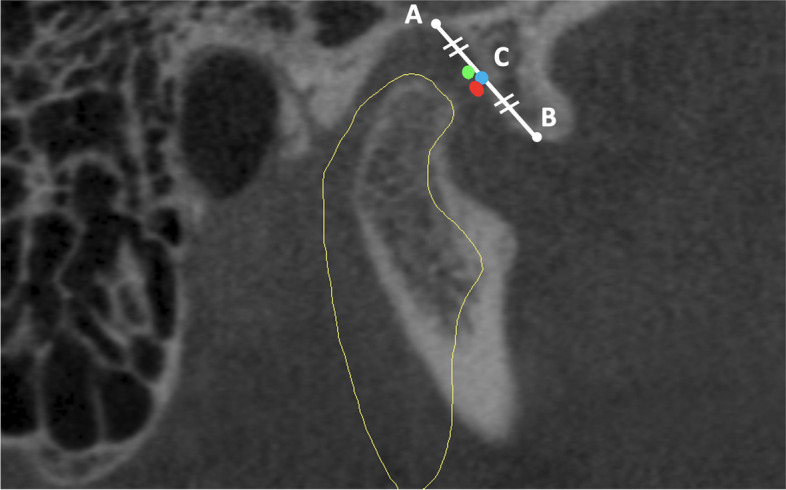

Background: This study aimed to investigate the range of angles and depths necessary for effective entry into the TMJ using CBCT images, focusing on classical Holmlund Hellsing points and a two-needle approach.

Methods: A retrospective cohort of CBCT images from January 2020 to November 2023 was analysed using 3D analysis to determine the variance in the required angles and depths.

Results: The average age of the 68 participants included in the study was 29.5 ± 11.1, 58.8% of the participants were female and 41.2% were male. The anterior needle measurements showed a relatively low standard deviation(SD) in depth(SD:3.6) with a low variance coefficient(12.5%), whereas the axial and coronal angles exhibited greater variability(SD:9.1 and 7.6, respectively). For the posterior needles, moderate SDs in depth(SD:3.5) and greater variabilities in axial and coronal angles(SD:9.6 and 5.3, respectively) were observed. A weak negative correlation was observed between the axial angle of the posterior needle and age(p: 0.028, Pearson r: -0.29) Anterior needle depth (p:0.037) and posterior needle axial angle(p:0.014) were greater in males than females. The anterior needle depth in patients with temporamandibular disease was greater than in those without(p:0,03).

Conclusion: There were significant differences in the angle measurements for both anterior and posterior needles, but lower variance in depth. The depths and angles of the needles did not correlate with age.